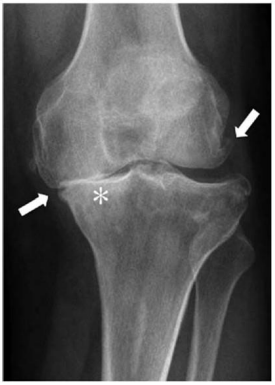

Uma paciente de 63 anos de idade compareceu ao consultório queixando-se de dor nos joelhos há cerca de cinco anos. Nega trauma. Refere que a dor começou a piorar nos últimos três meses. Relata ainda diabetes mellitus, e que seu joelho começou a entortar (sic) e que, quando acorda, o seu joelho frequentemente está rígido.

Considere que a paciente do caso clínico relatado realizou o exame representado na figura. De acordo com a classificação de Kellgren e Lawrence, trata-se do grau